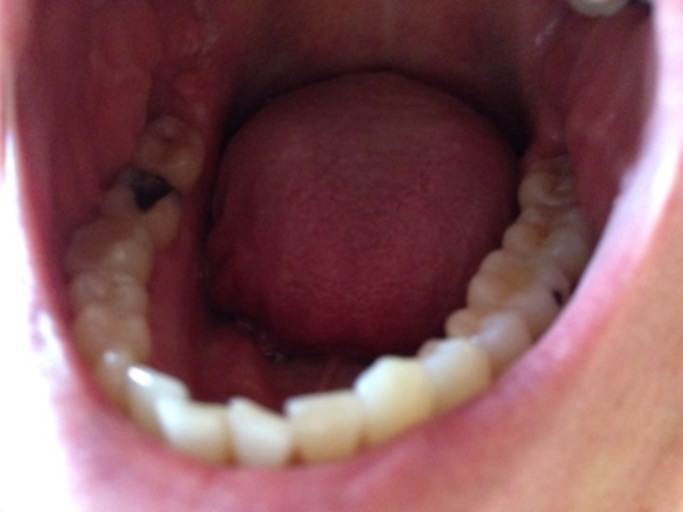

Small Cavity in the Lower Right Molar

Hi there, I am Zaldi and a student at Boise State University, I have a small cavity on the lower right molar tooth, - I want to know how much a filling or cavity treatment is for this case, and - I want to ask if there is any schedule that I can...